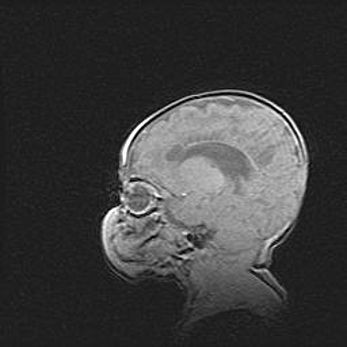

Наружная гидроцефалия с возможной атрофией височных областей.

Возраст: 28 дней

Вес: 3670 г

Пол: мужской

Окружность головы: 38 см

Срок гестации: 40 недель

Гидроцефалия головного мозга у новорожденных – это заболевание, которое характеризуется скоплением избыточного количества спинномозговой жидкости в желудочковой системе головного мозга в результате затруднения её перемещения от места выработки к месту поглощения в кровеносную систему или вследствие нарушения абсорбции. При открытой наружной форме гидроцефалии у новорожденных расширяются и переполняются субарахноидные пространства.

При нормотензивных  формах,  которые,  как  правило,  являются  следствием  перенесенных ишемических  повреждений  паренхимы  мозга,  возможно  сочетание микроцефалии  с нормотензивной гидроцефалией. В основе данных изменений лежит атрофия больших полушарий с преимущественной  локализацией  в  лобно-височных  областях.